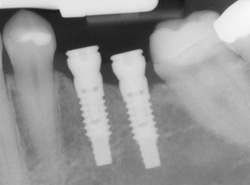

An implant is a synthetic tooth root in the shape of a post that is surgically placed into the jawbone. The “root” is usually made of titanium, the same material used in many replacement hips and knees, and a metal that is well-suited to pairing with human bone. A replacement tooth is then fixed to the post. The tooth can be either permanently attached or removable. Permanent teeth are more stable and feel more like natural teeth.

Implants are versatile. If you are only missing one tooth, one implant plus one replacement tooth will do the trick. If you are missing several teeth in a row, a few strategically placed implants can support a permanent bridge (a set of replacement teeth). Similarly, if you have lost all of your teeth, a full bridge or full denture can be permanently fixed in your mouth with a strategic number of implants.